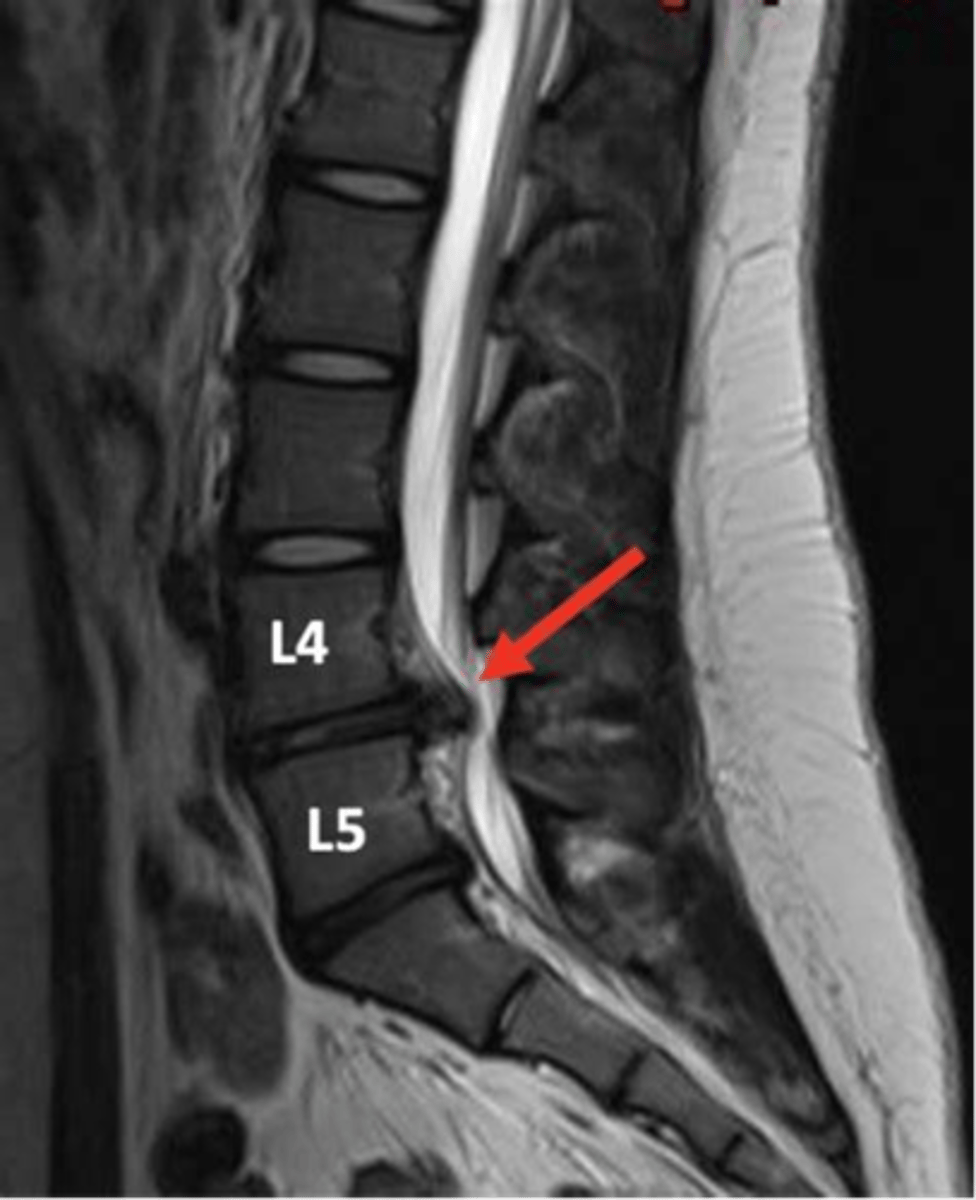

spondylolisthesis

forward slipping of one vertebra over another (caused by vertebral fracture at the pars interarticularis)

spondylolithesis can be caused by ____ or ______

degenerative or traumatic etiology

spondylolisthesis s/s can range from none to _______

severe low back pain with radiculopathy